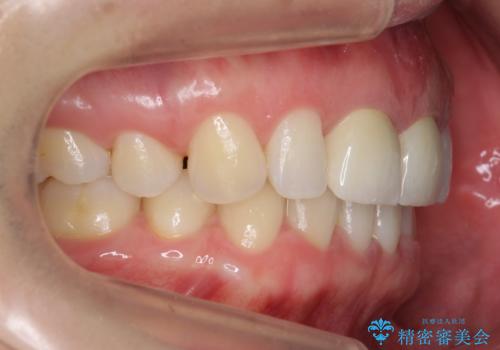

開始前

- 前歯が2本出っ歯だったのを、他院でセラミックにしたが、口元が突出しているのが治らないとのことでした。

セラミックにする際に神経をとり、無理やり歯の頭の部分のみ内側に引っ込めてありました。

出っ歯が厳しい方は、歯の頭の部分だけ被せて角度を変えても、根元は変わらないため、口元は下がりません。